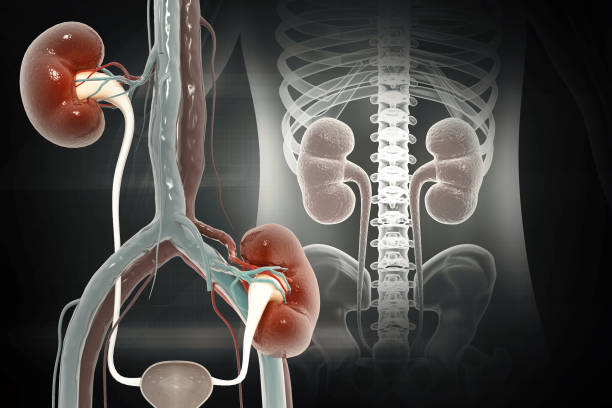

신우신염이란? 상부 요로계에 생긴 세균 감염

신우신염은 **신장과 신우(renal pelvis)**에

세균이 침투해 염증이 발생하는 감염 질환입니다.

대부분 하부 요로계, 즉 방광이나 요도에서 시작된 세균이

상행성으로 올라가 신장 부위까지 확산되며 생깁니다.